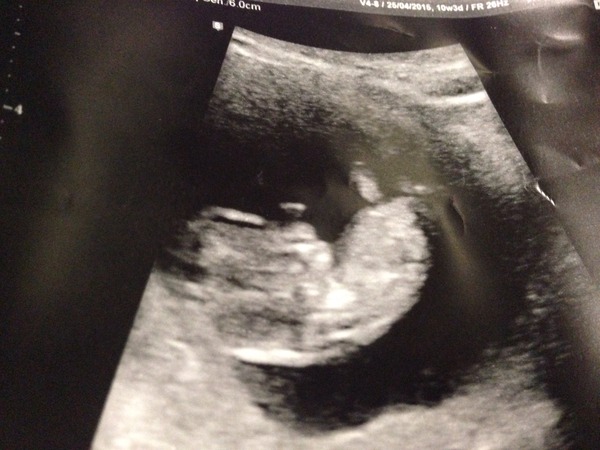

That is a lovely pic jelly